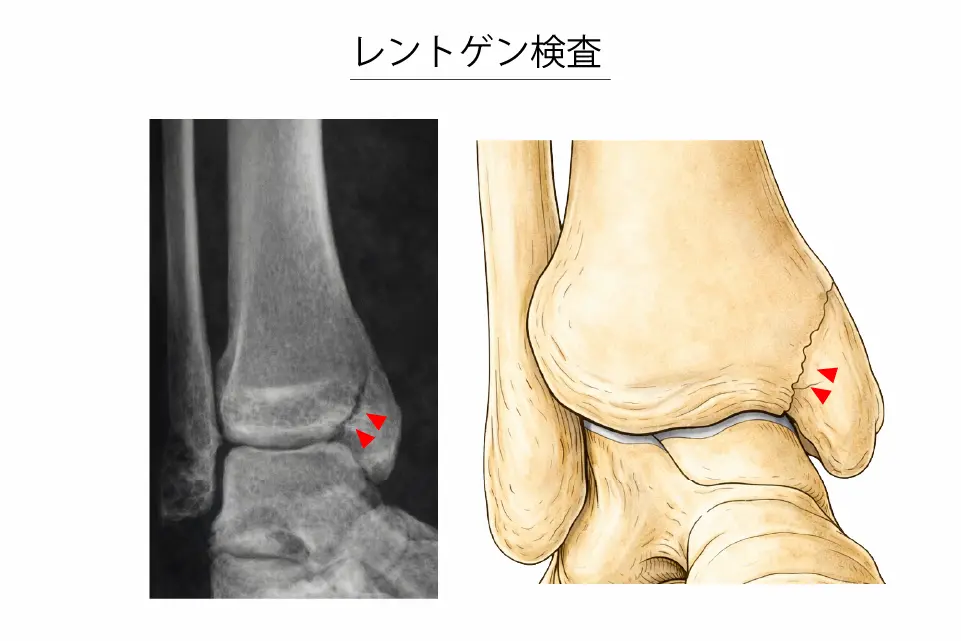

レントゲン検査(整形外科による)

- 早期は異常が写らないことが多い

- 特徴的所見:脛骨天蓋と内果関節面の境界から垂直に内上方へ向かう骨折線